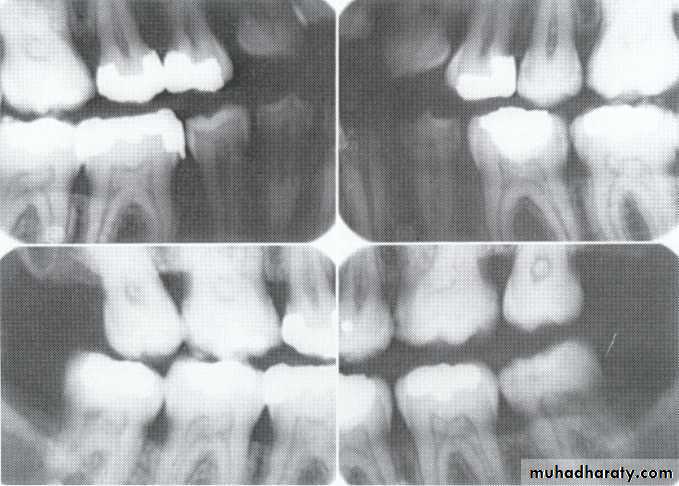

Congenital syphilis develop dental hypoplasia that involves the permanent incisors (Hutchinson's teeth )and first molars (mulberry molars).

* Hutchinson’s Incisor

lateral incisors are peg-shaped or screwdriver-shaped.

widely spaced.

notched at the incisal edge.

with a crescent-shaped deformity

Characterized by multiple rounded rudimentary enamel cusps on permanent 1st molars.

dwarfed molars with cusps covered with globular enamel growths giving the appearance of a mulberry.* Mulberry Molar